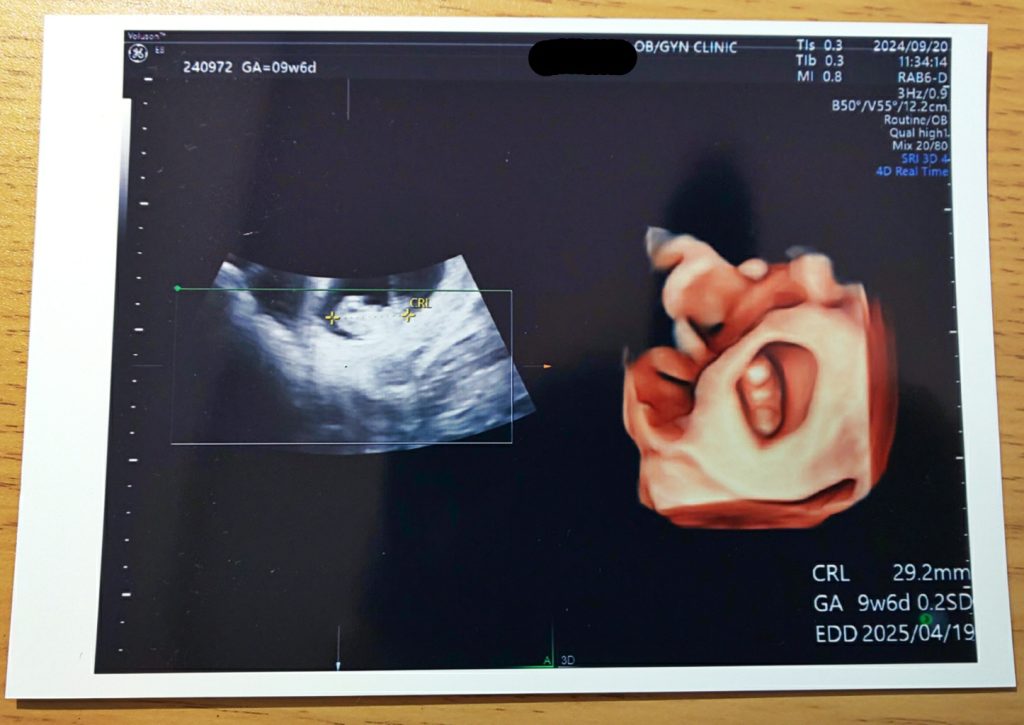

09/20 9w6d 全長29.2mm

平均の成長具合。頭、手、足ができていてへその緒も見えました!つわりが酷くてゼリーとお茶しか摂取できなかったけど順調に育っていて一安心。毎日吐き気があり、寝たきりで仕事にすら行けない状態が続いているため、1ヵ月休職の診断書が出ました。